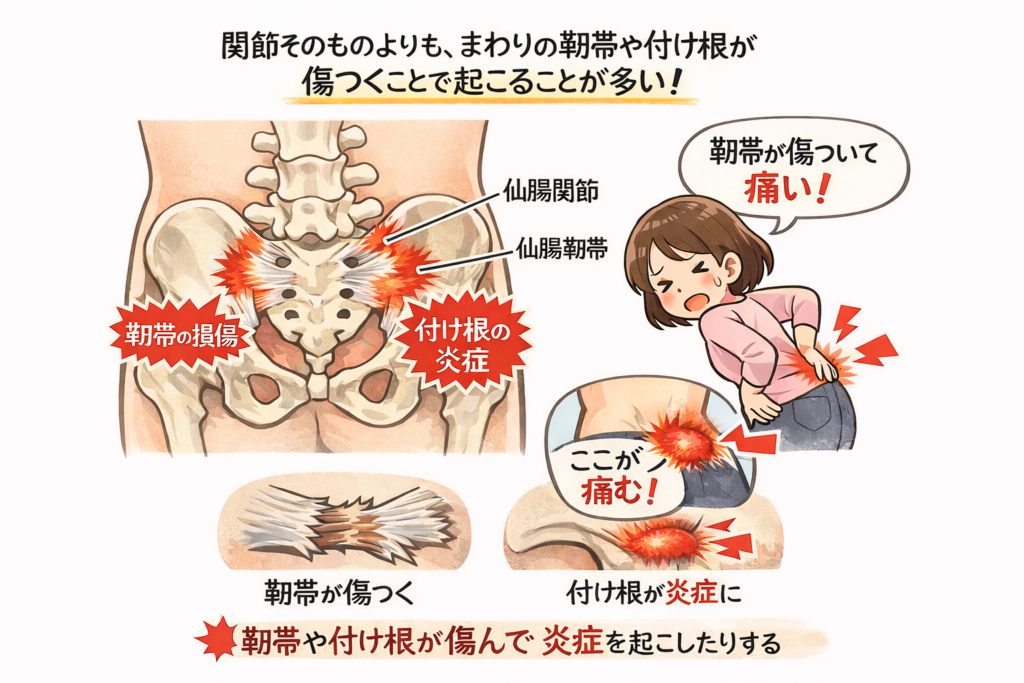

仙腸関節の痛みは、関節そのものよりも、まわりの靱帯や靱帯の付け根が傷つくことで起こることが多いと考えられています。

たとえば、片脚で体重を支えたときや、前かがみの姿勢が続いたときには、仙骨が前に傾こうとします。この動きが強くなると、後ろ側の靱帯が引っぱられ、小さな傷や炎症(えんしょう・組織が熱をもってはれる反応)が起こります。

この関節は、前側にある関節部分と、後ろ側で骨どうしを強く支えている靱帯(じんたい)という組織でできています。

靱帯とは、骨と骨を結びつけて体を安定させるゴムのような組織のことです。仙腸関節はこの靱帯によってとても強く固定されているため、大きく動く関節ではありませんが、わずかに動くことで歩いたり立ったりする動作を助けています。